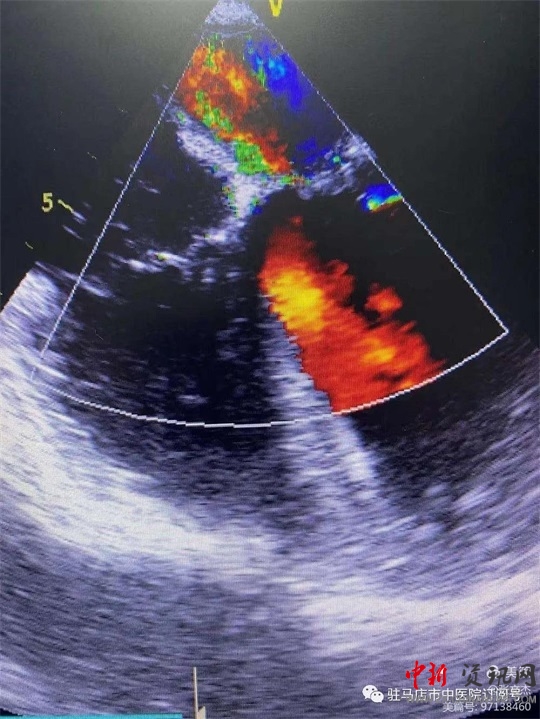

術(shù)前經(jīng)食道心臟超聲

復(fù)跳后經(jīng)食道心臟超聲,二尖瓣功能較術(shù)前明顯改善。